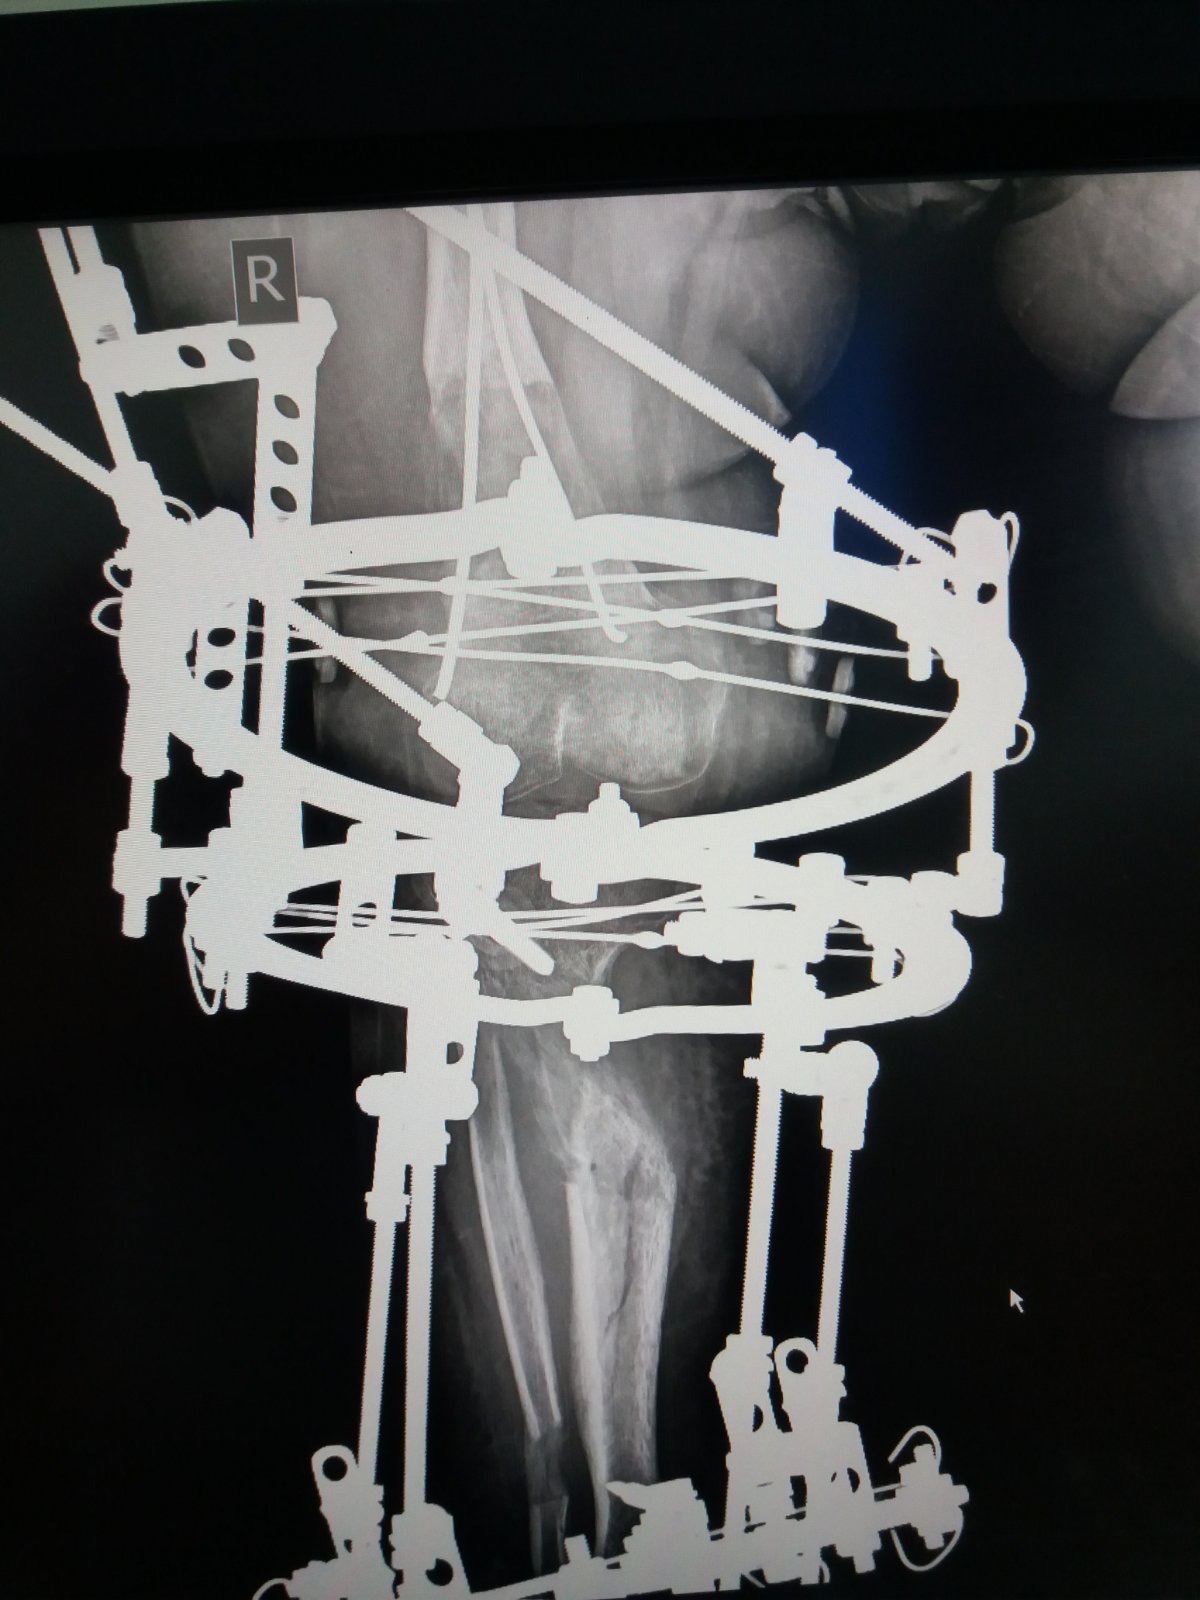

You can see the results of the treatment on the video. This was on January 2nd last year. When we looked and saw that the lengthened bones had grown properly and then we took off Ilizarov’s apparatus. It was necessary to wear the plaster for a certain time, so that the patient could use her leg without any fear. Also, to start walking in the period from when we removed the device until this examination. In the future, she should do exercise for the knees, ankle, and to strengthen her muscles.

The right doctor was found in the Atlas Hospital in Belgrade. Dad Nusret showed us a picture where you can see how big the problem was with Elma’s legs. They were in the shape of the letter O, and in the case of the left, the deformity was greater because the bone in the axis was completely inverted. After the operation and wearing the apparatus they are corrected now and parent’s happiness is endless. Every inch was important to them.